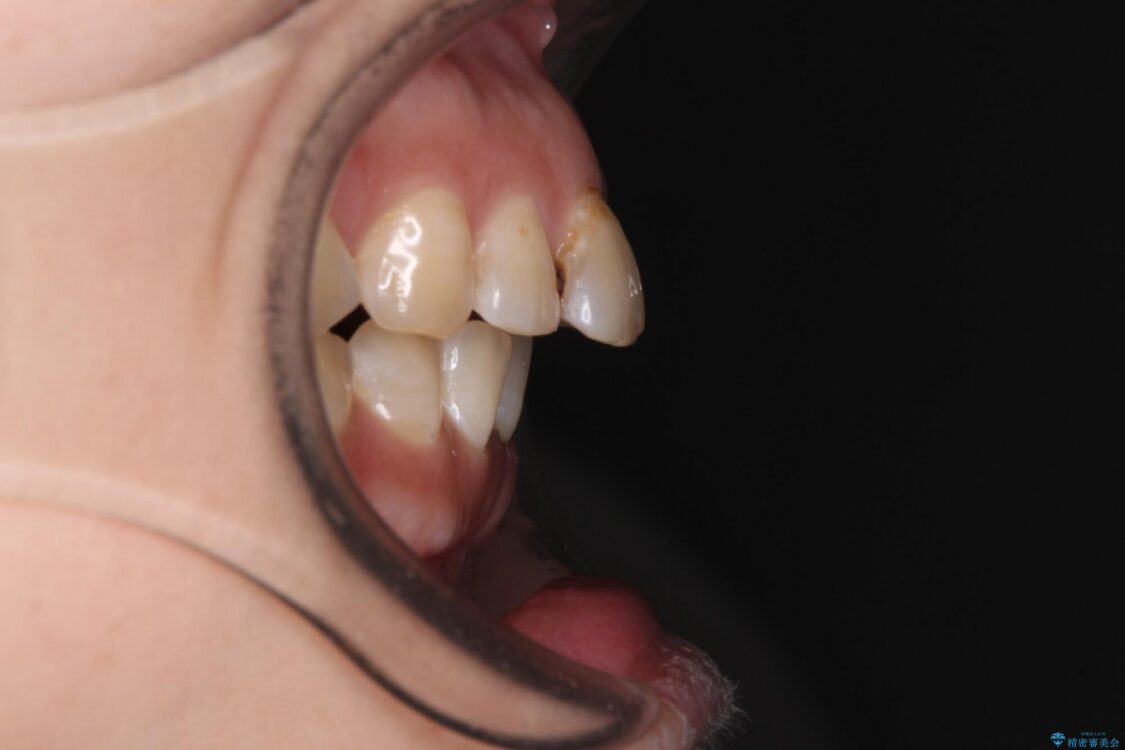

治療前

飛び出た上の前歯を気にして来院された患者様です。

奥歯の咬み合わせは、上顎歯列が理想的な一よりも数mm前方にある状態でした。

舌の突出癖が原因で上下の歯に大きなスペースが生じていたため、舌のトレーニングをしっかり行っていただくことで、上顎歯列をスムーズに移動させることができました。